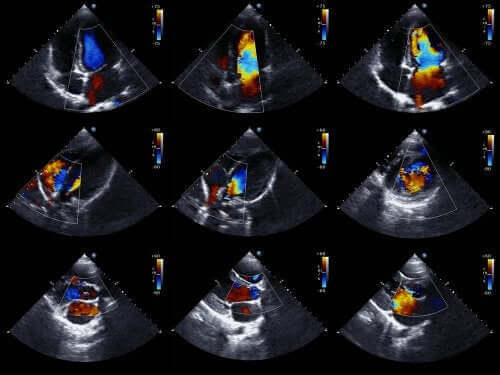

Doktorlar genellikle bu sayede bebek doğmadan önce bu tür anomalileri teşhis edebilir. Bunu yapmak için fetal ekokardiyogram kullanırlar. Bu, hareketli kalp görüntüsünü yeniden yaratmak için ses dalgalarını kullanan bir tekniktir.

Bu sayede kalbi görebilir ve bir bebek hala rahim içindeyken kalp işlevlerini inceleyebiliriz. Bu bilgilerle doktorlar doğumdan hemen sonra tedaviyi programlayabilir.